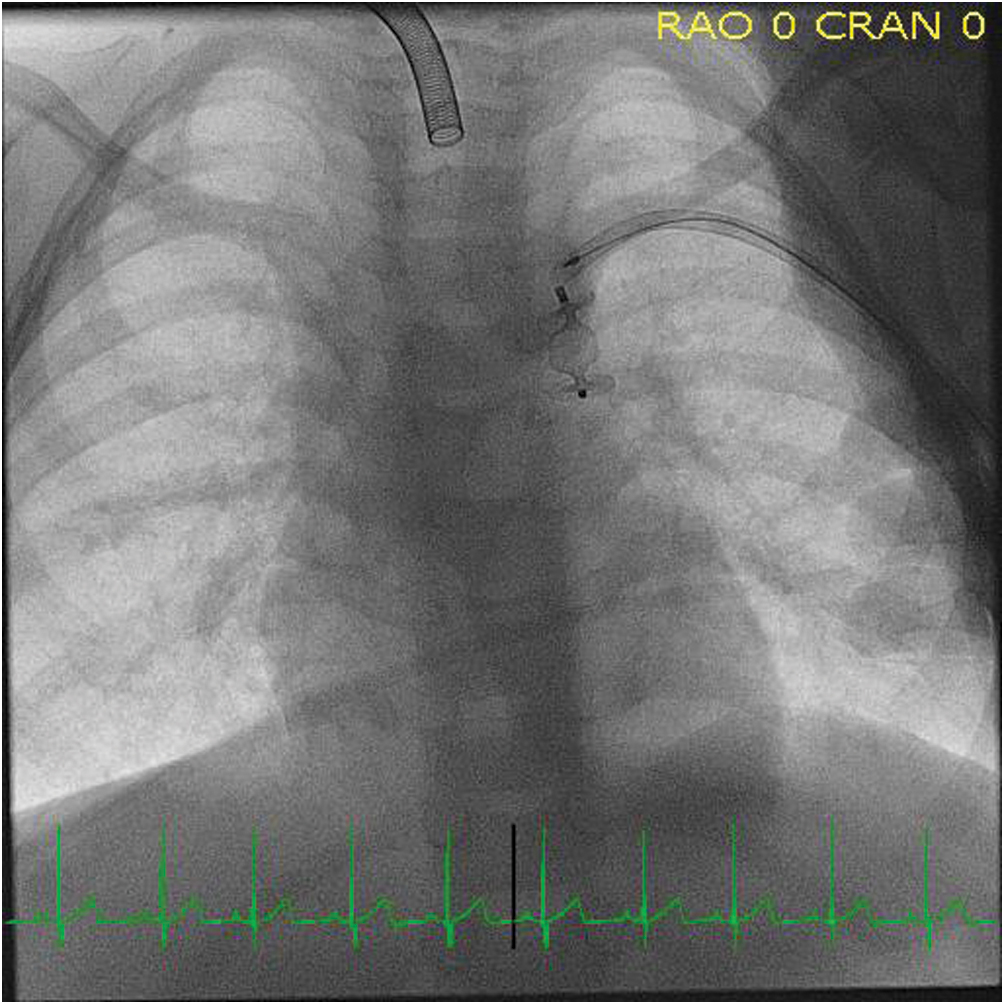

The patient subsequently underwent cardiac catheterization. Angiography confirmed earlier imaging findings (Fig. 3), and the PLSVC was successfully occluded with a 10 mm Amplatzer Vascular Plug II distal to the bridging vein (Fig. 4). Following the procedure, the patient’s positional hypoxemic episodes resolved. The patient has weaned off mechanical ventilation during the day, and is currently weaning from respiratory support during sleep.

Figure 4: Fluoroscopic image during cardiac catheterization confirming correct placement of vascular plug in the PLSVC